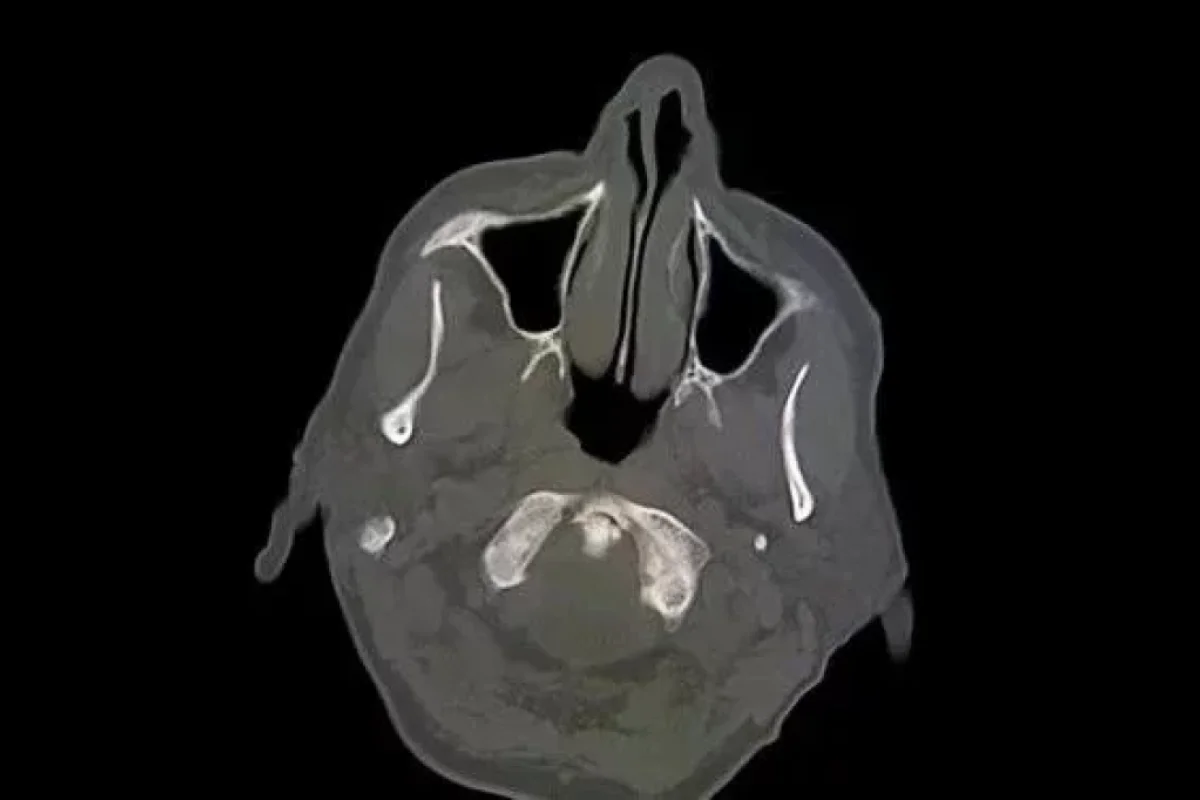

Beyin tomoqrafiyası zamanı məlum olub ki, kişinin beyninin yarısı yoxdur və onun kəllə sümüyündə nazik beyin toxuması və maye təbəqəsi var. Bu xəstəlik "Hidrosefali" adlanır. Koqnitiv psixoloq Aksel Kliremans qeyd edib ki, kişi normal həyat sürüb, ailəsi olub və işləyir. Şikayət etdiyi zaman alınan IQ testinin nəticəsi 84 olu, bu normal diapazondan bir qədər aşağıdır.

Həkimlər hesab edirlər ki, onun xəstəliyinə səbəb 30 il ərzində beynində yığılan maye olub və bu maye onun beyninin böyük hissəsinin məhv olmasına səbəb olub.

Digər tərəfdən xəstəlik körpə olanda aşkarlanıb və stent qoyulub. Lakin 14 yaşında ikən stent çıxarıldıqdan sonra beyninin çox hissəsi aşınmaya başlayıb. Keçmişdə şüurun beynin xüsusi sahələri ilə əlaqəli olduğu düşünülürdü, lakin bu cür həyat hekayələri şüurun yalnız xüsusi bir bölgə tərəfindən idarə olunmadığını iddia edən yeni nəzəriyyələrin ortaya çıxmasına səbəb oldu.